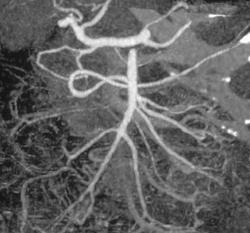

Stenosis of Celiac Axis